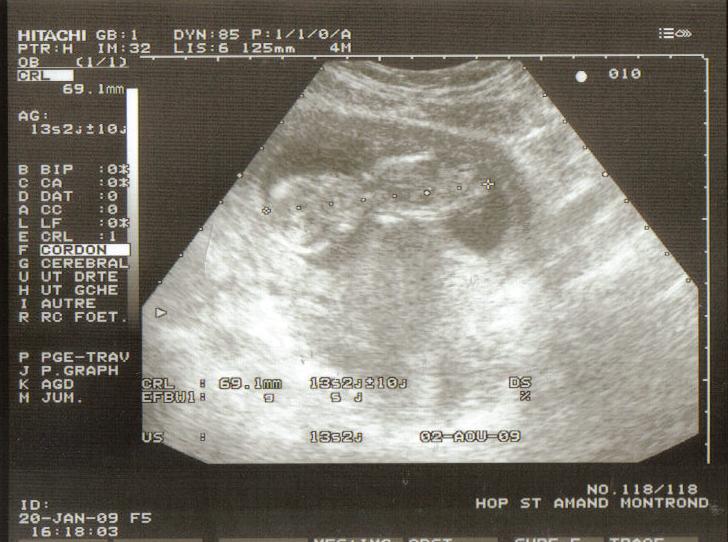

1 pièce(s) jointe(s)

Dernière photo du petit prodige!!! Regardez d'où elle est prise et déduisez en ce que vous voudrez!!!:ok::ok::ok::ok::ok::ok:

Mais pourquoi? non je vais être maman de mon petit Hugo et j'en suis fière!!! d'ailleurs regarde mon fils te montre son cul mdr:roule::roule::roule: